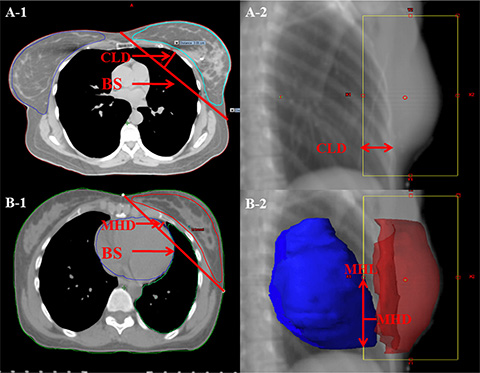

A number of studies have utilized anatomic parameters to evaluate the doses to the organs at risk(OAR) in whole breast irradiation using 3DCRT and other modified IMRT [13, 28–36]. In order to explore the selection criteria for patients who will benefit from eComp based treatments, the anatomic features including breast separation (BS), central lung distance (CLD), maximal heart distance (MHD) and maximal heart length (MHL)were measured in a DRR view of one of the fields (Figure 8). The BS was defined as the distance between entry points of two opposing beams on the central plane. The CLD was defined as the maximum perpendicular distance from the posterior edge of the tangential field to the posterior part of the anterior chest wall in the middle of the field. The MHD and the MHL were defined as the maximal width and length of the heart contour intercepted by the posterior boarder of the tangential fields.

Figure 8: Anatomic parameters. (A) PTV was contoured in red. The breast separation (BS) is the distance between entry points of two opposing beams on the central plane. The central lung distance (CLD) is the perpendicular distance from chest wall to the posterior boarder of the tangential fields. (B) The heart was contoured in orange. The maximal heart distance (MHD) and the maximal heart length (MHL) are the width and length of the heart contour intercepted by the posterior boarder of the tangential fields.